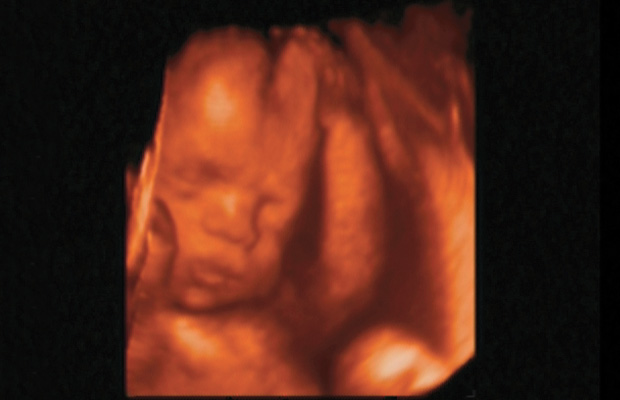

2004 yılında İstanbul’da katıldığım bir Ultrasonografi kongresinde ilk kez 4 boyutlu ultrason ile tanıştım. Bu kongrede anlatılanlardan ve görüntülerden çok etkilendim. Ultrason’u ilk bulan kişinin, gelişmelere bakarak bu konuda daha fazla bir şey yapılamayacağını söylemesi dikkatimi çekti. Ancak o dönemde bilgisayarın olmadığı, aslında 4 boyutlu ve renkli görüntülerin bilgisayar sayesinde oluşturulduğunu öğrendim. Bilindiği gibi Ultrason cihazı sadece ses dalgaları ile çalışan ve hiçbir yan etkisi olmayan bir tanı yöntemidir. 4 boyutlu ultrasonografide de farklı bir dalga boyu gönderilmemekte, 4 boyutlu görüntüyü oluşturan bilgisayar sistemi olmaktadır. Evrende 3 boyut vardır. 3 boyutlu ultrasonda anne karnındaki bebeğin görüntüsü anlık görüntü şeklinde alınır ve 3 boyuttan incelenir. Aynı zamanda bu görüntüden çok ince kesitler alınarak bebeğin iç organları da incelenebilmekte ve anomali (sakatlık) taraması en ince ayrıntılarına kadar yapılabilmektedir.

Evrendeki 4. Boyut ZAMAN boyutudur. Yani ultrasondaki bu 3 boyutlu görüntüyü bebek hareket ederken de alabiliyorsanız o zaman bu görüntü 4 boyutlu olmaktadır. Kısaca anne karnındaki bebeği hem her yönden, hem de hareketli olarak görebiliyorsanız buna 4 boyutlu ultrasongrafik inceleme denir. Bebeğin gerçek görüntüsünü alabiliriz ve doğum sonrasındaki resimlerle bu görüntüler bire bir eşleşmektedir.

Aynı zamanda bebeklerin renkli görüntülerinden bir fotoğraf arşivi düzenledim. Bu fotoğraflardaki ve filmimdeki bebek görüntülerine de birer isim vererek, o anda ne yaptığını biraz da mizahi olarak yorumlayarak ekledim.